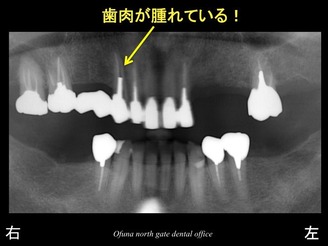

上顎右側の犬歯部が腫れているとのことで来院されました。

診査の結果、歯根破折 していることが分かりました。

同歯は抜歯になります。

今回の症例でも 非常に大きな骨吸収が起こっていました。

一般的に歯肉が腫れるような状態の場合には、

骨吸収が起こっていると考えられます。